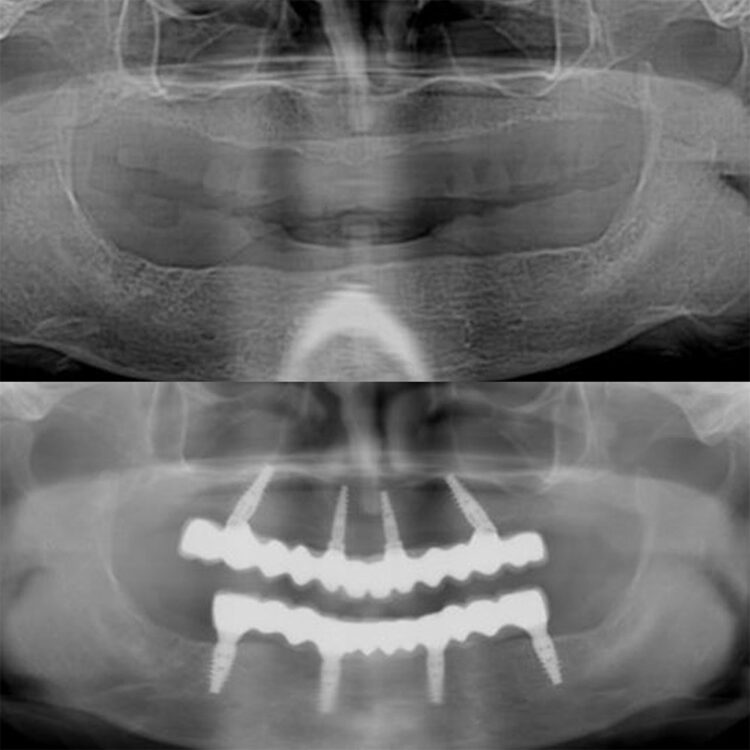

First of all a detailed clinic and radiological examination should be done to patients for who All On Four treatment is planned. By making meausrements through computerized tomography (BT) a suitable plan is made for the patient.

All On Four procedure is composed of two parts as surgery and dental prothesis process. After 4 pieces of dental implants are applied to the patient on the first day of treatment, temporary dental prothesis is fixed on dental implants on the same day. 3 months later permanent teeth prothesis is applied to patient